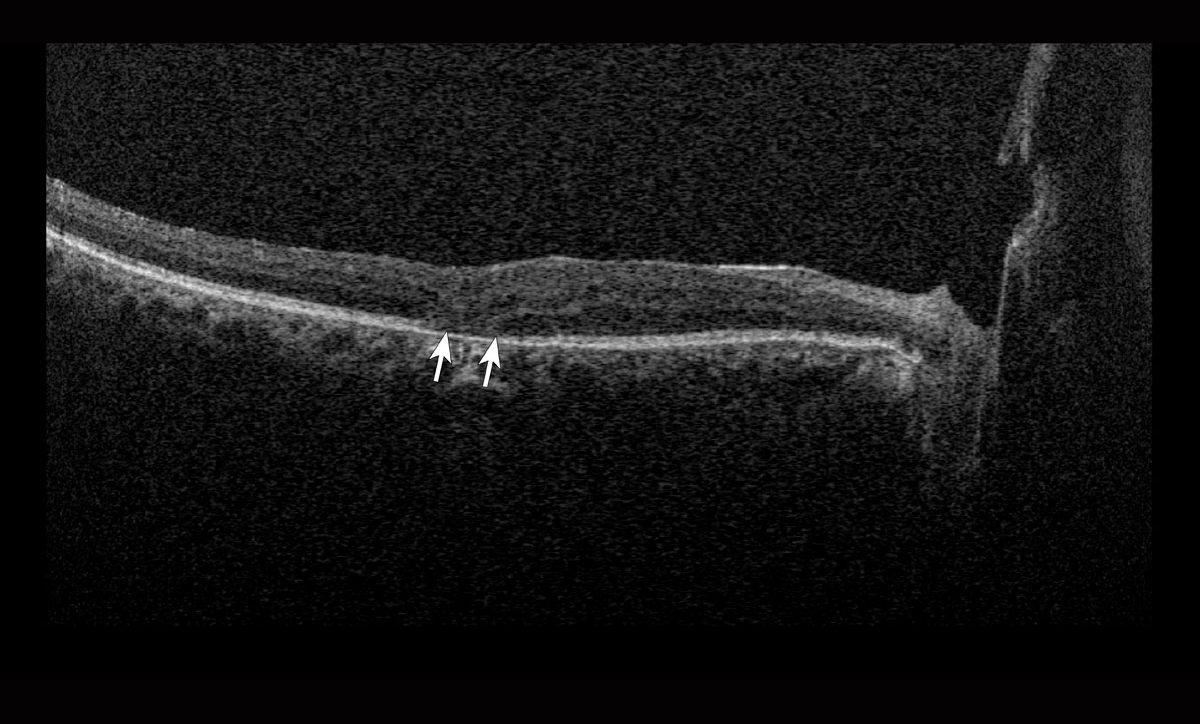

Los cambios patológicos más específicos, como la desorganización de las capas internas de la retina (DRIL; Figura 1), solo pueden apreciarse mediante OCT y se han identificado como marcadores del potencial visual y predictores de la progresión de la RD.4 Del mismo modo, la alteración de la retina externa (Figura 2) y el daño temprano de los fotorreceptores pueden indicar una enfermedad más avanzada con un pronóstico visual desfavorable.5

Figura 2. Tomografía de coherencia óptica de un paciente de 59 años con antecedentes de retinopatía diabética proliferativa que muestra una alteración de la retina externa (flechas).